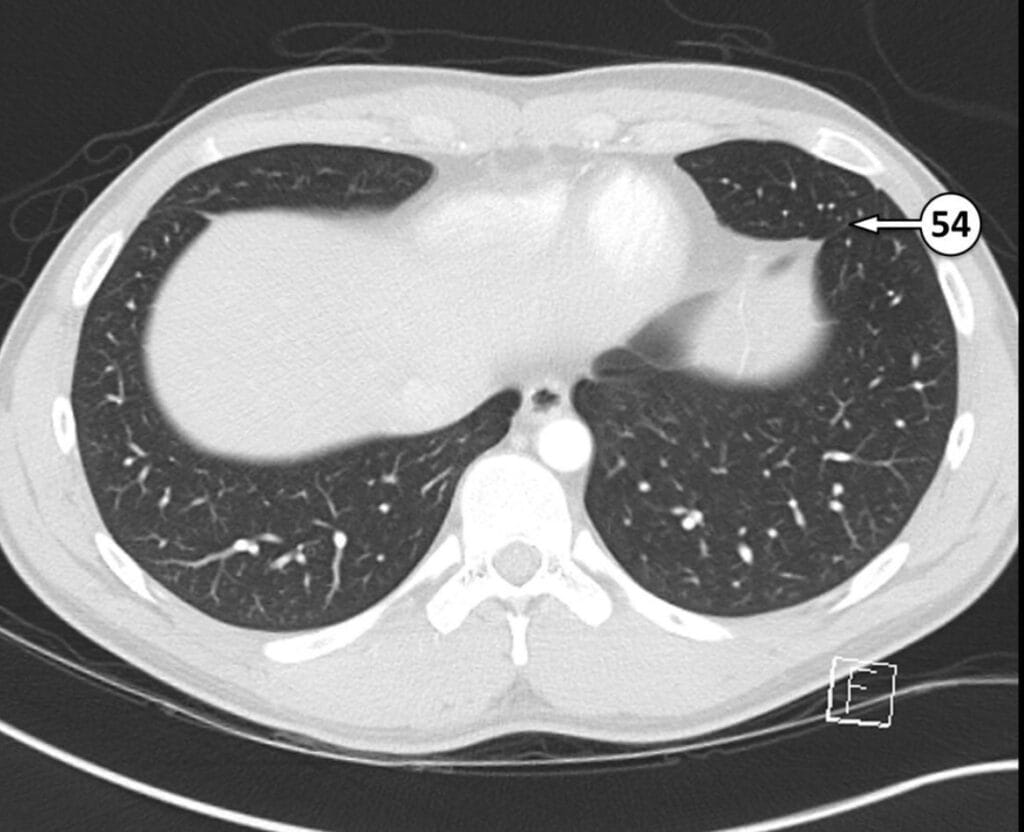

54. accessory fissure